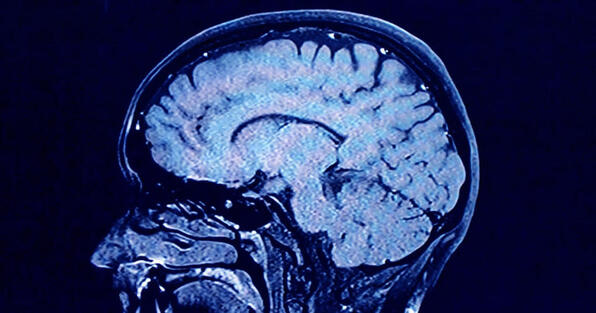

Human brains have 5 distinct 'epochs' in a lifetime, study finds

During each of these phases, our brains show markedly different characteristics in their architecture, according to the new findings. CONTINUE...